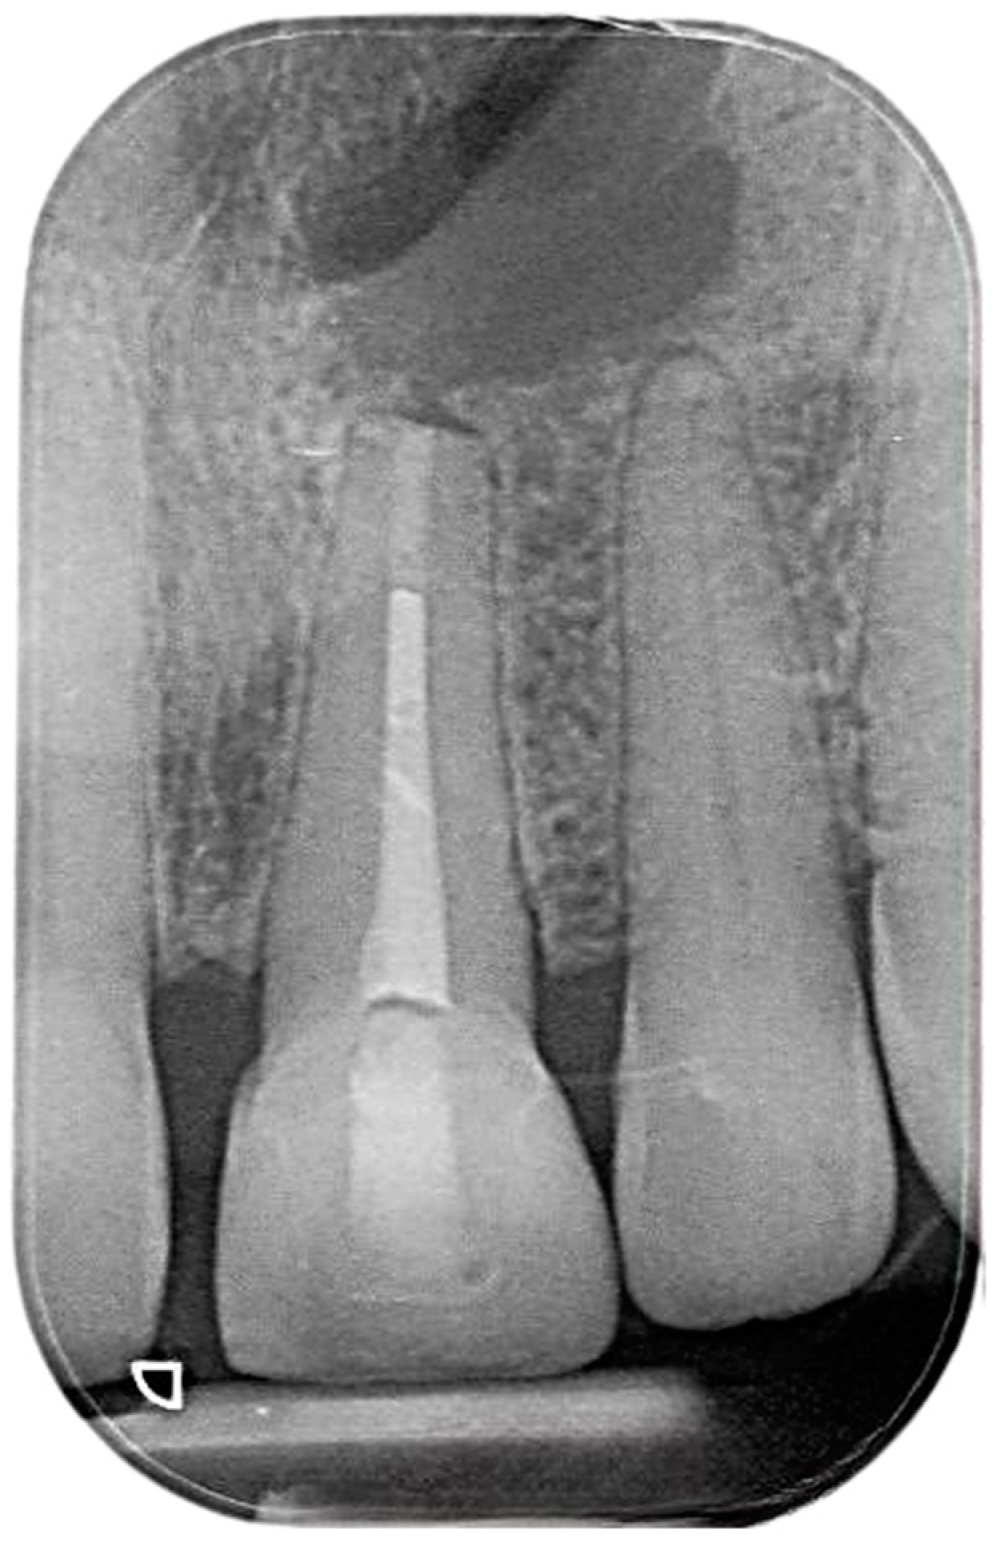

2.2. Delivery of Treatment

2.4. Healing of the Defect and Follow Up